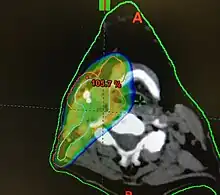

CT scan in transverse plane, viewed from below, showing a contrast enhancing right tonsil mass due to HPV+OPC